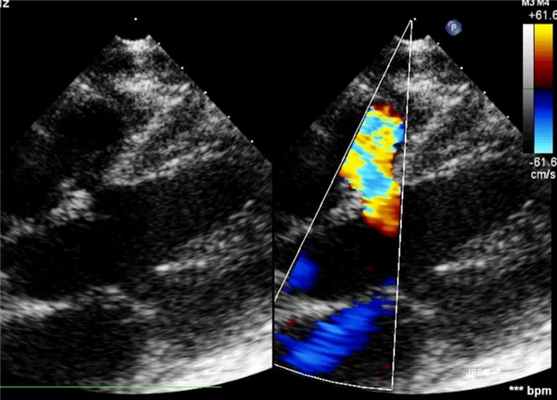

Диагноз ставят на основании результатов эхокардиографии. Определяют в В-режиме, цветном доплеровском картировании наличие, количество, размер и расположение дефектов, с помощью спектрального доплера можно определить скорость потока сквозь дефект, направление сброса и давление внутри камер сердца.

Р ис. 1 ДМЖП в В-режиме.

Рис.2 ДМЖП в В-режиме и режиме ЦДК.